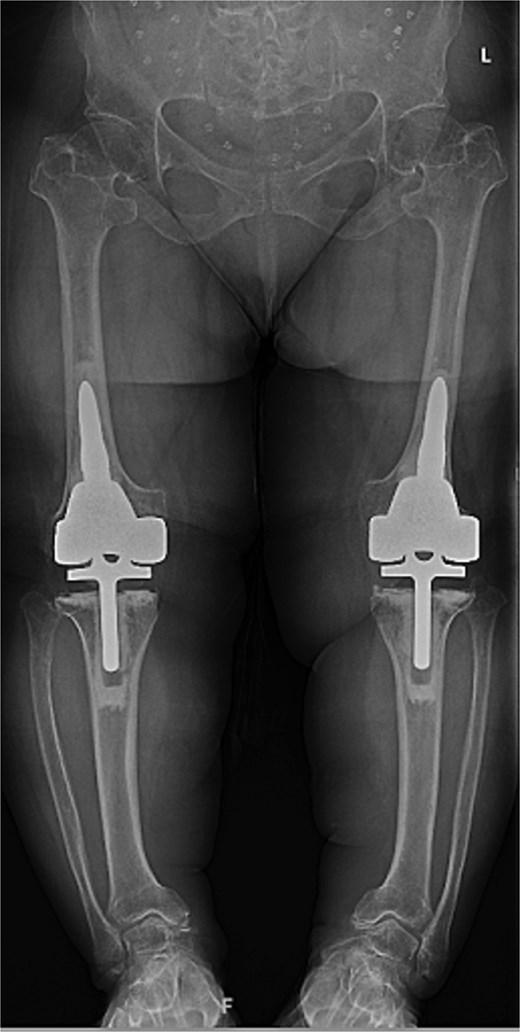

At the 2-year follow-up, the patient reported no significant pain, demonstrated a normal gait, and had active bilateral knee range of motion from 0° to 125°. There was no joint line tenderness or instability. Surveillance radiographs confirmed well-aligned and stable components with no evidence of implant failure or periprosthetic lucency (Fig. 3). At the five-year follow-up, the patient remained very satisfied with her knees and denied knee pain. On exam, her gait was slightly antalgic, but active bilateral knee range of motion remained preserved at 0° to 120°, and both knees remained stable throughout range of motion and nontender to palpation. Radiographs continued to show stable prosthetic components without evidence of implant failure or periprosthetic lucency (Fig. 4).

Two-year postoperative AP radiographs demonstrating stable, well-fixed components with appropriate alignment and no evidence of implant loosening or periprosthetic lucency.